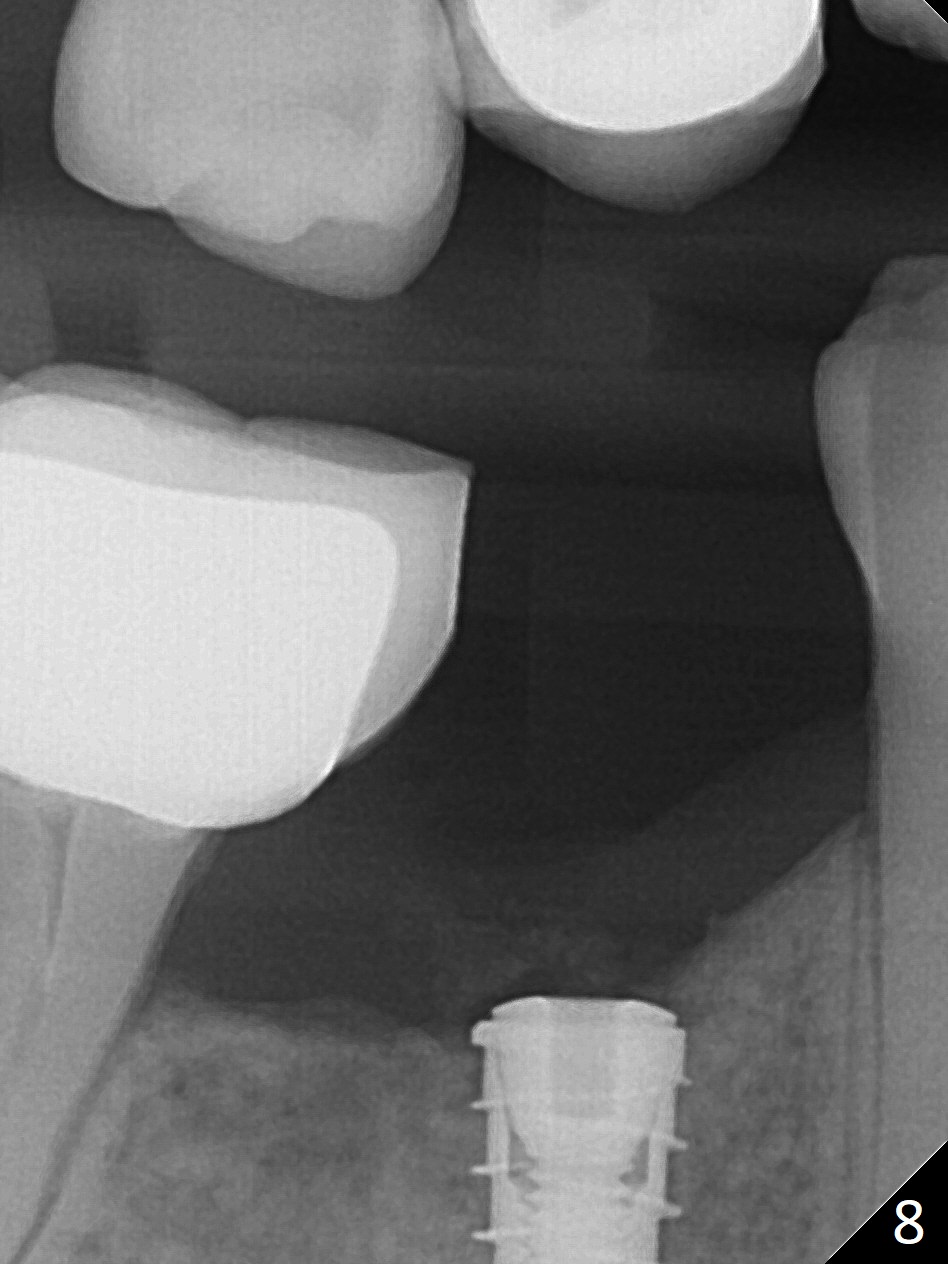

The patient returns for implant placement 11 months post extraction of #28 and 29. With flapless manner, initial osteotomy happens to drop into the original socket of #28 (Fig.4). After use of 3.3 mm Magic Drill (MD) and Final Drill for 15 mm, a 4x11 mm dummy implant is placed (Fig.5). It appears that the implant is long for the site (red dashed line: Mental Loop). However, a definitive implant (4x9 mm, IBS) has difficulty to reach its depth (Fig.6). After several rounds of untorque and retorque, the implant does not seat completely (Fig.7, implant driver disengagement) with autogenous bone placed distal (>). Retrospectively, a larger MD should have been used (3.8 mm) for complete seating in the dense bone. In fact she is post breast cancer treatment with 50% chance of relapse. The patient returns for follow up 1.5 months postop (Fig.8). The wound has healed. Impression is taken 5 months postop (Fig.9). When the crown is cemented, food impaction is an issue between the implant crown and crown at #30. Since the tooth #30 is mesially tilted with distal open margin and apical infection, the tooth will be extracted. Osteotomy is going to be initiated in the mesial slope of the mesial socket (Fig.9 red line). An implant will be placed more or less in the mesial socket (green box).